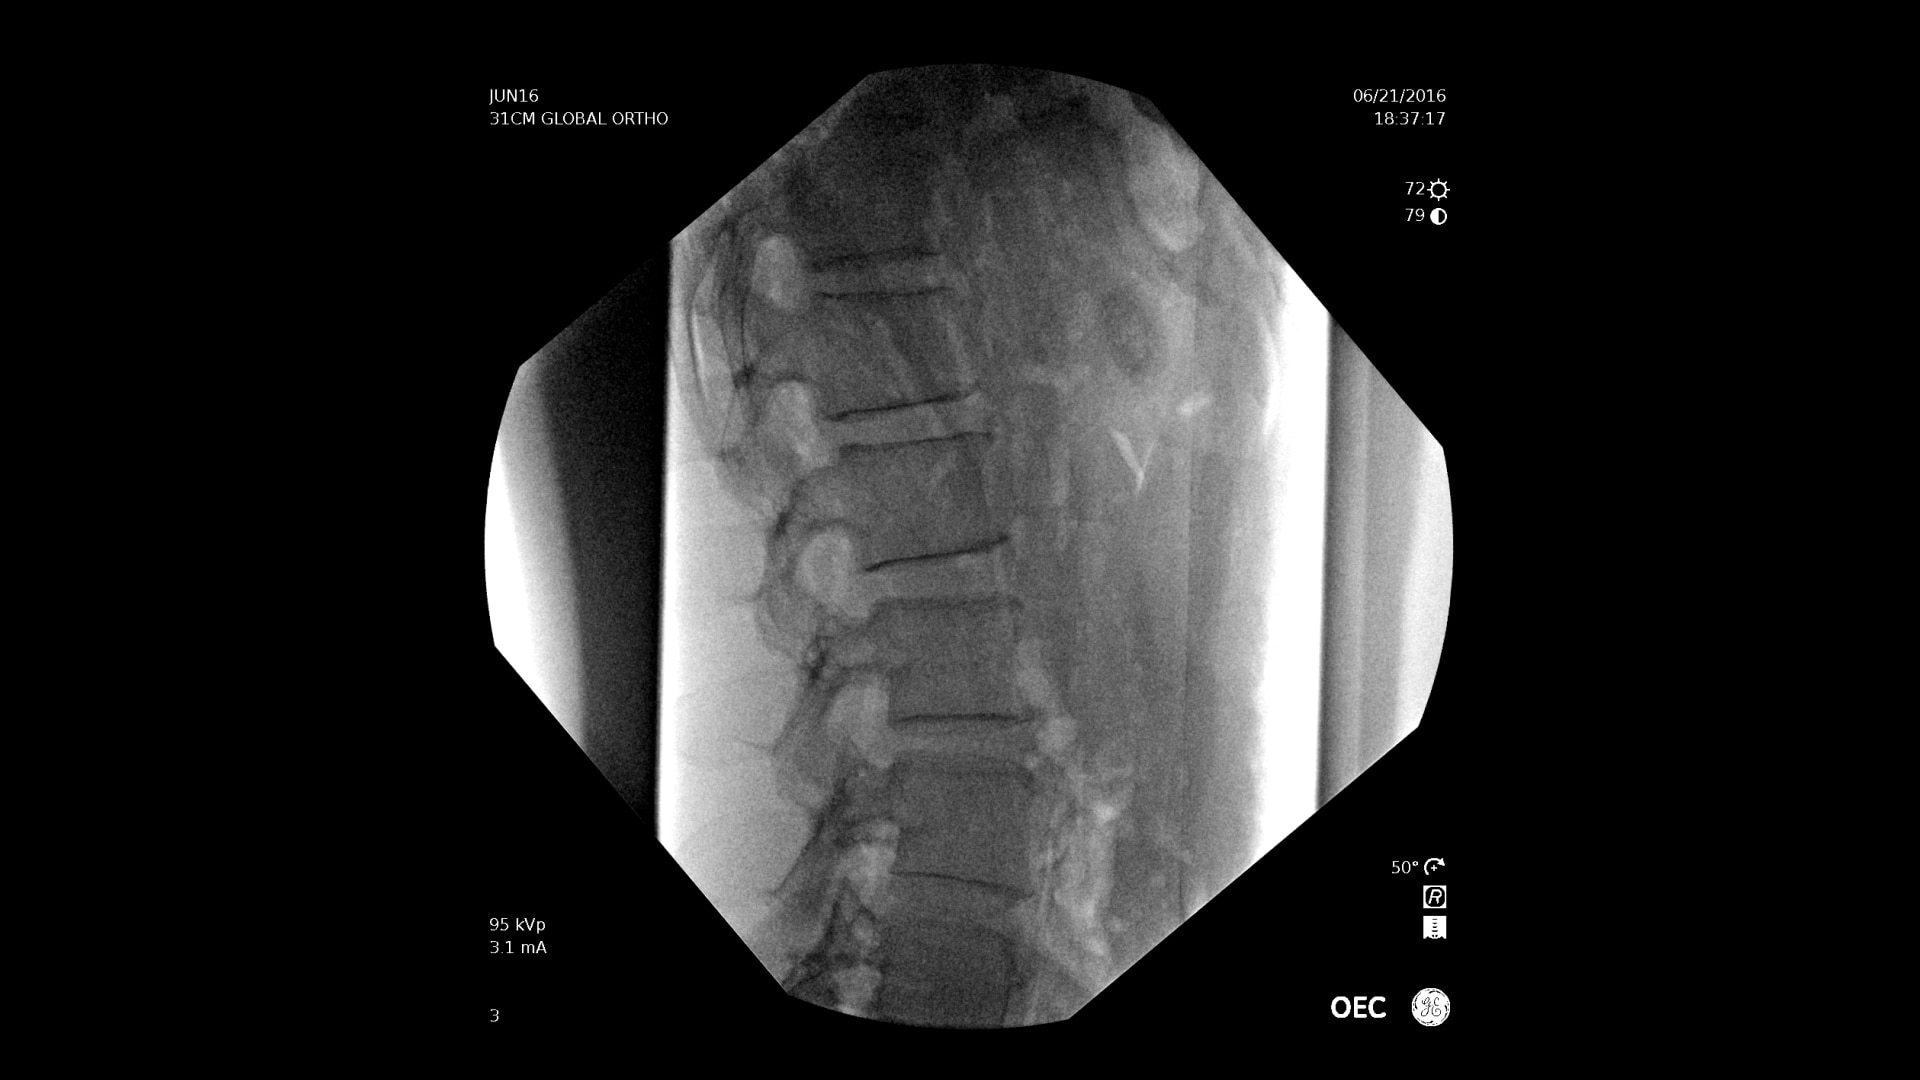

With choice of C-arms to fit a variety of needs, easily obtain challenging spine angles with a 55° overscan, rainbows without moving the base, or a motorized drive.

Experience the benefit of a large field of view up to 22%* larger with the OEC Elite X-ray housing design that enables the detector to get closer to the patient.

OEC C-arms perform imaging in a variety of procedures such as:

• Thoracolumbar procedures